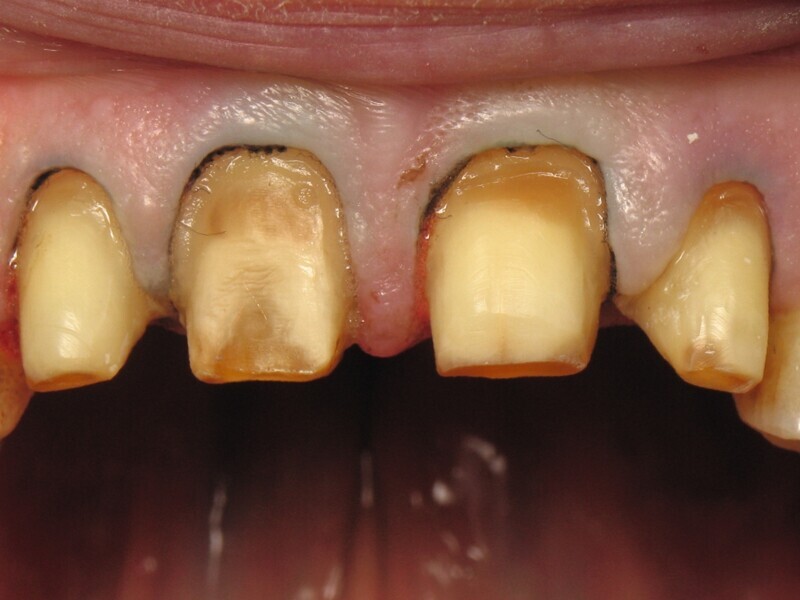

Une semaine auparavant, les figures 8 et 9 montrent la préparation dentaire et le placement du premier fil de rétraction gingivale. La forme de préparation a laissé une marge suffisante pour le prothésiste, afin de concevoir les couronnes. Le fil de rétraction gingivale a été place pendant la phase de préparation, afin de ne pas blesser la gencive cervicale, mais aussi pour la déplacer apicalement. Ainsi il a été possible de réaliser des limites juxta-gingivales, respectant l’anatomie dentaire et la sante parodontale. Il est intéressant de constater que la teinte dentaire n’est pas homogène entre les dents et au sein même de la dent, nous allons remonter dans le temps pour comprendre ce phénomène.

Fig. 8 : Préparation dentaire et rétraction gingivale.

Fig. 9 : Vue rapprochée de la préparation dentaire et de la rétraction gingivale